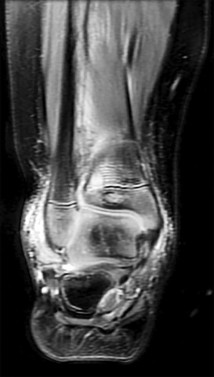

Question 49

A 12-year-old boy presents with a history of recurrent ankle sprains and a rigid, painful flatfoot. Radiographs demonstrate an "anteater nose" sign.

Which radiographic view is most sensitive for confirming the exact location of the most likely coalition?